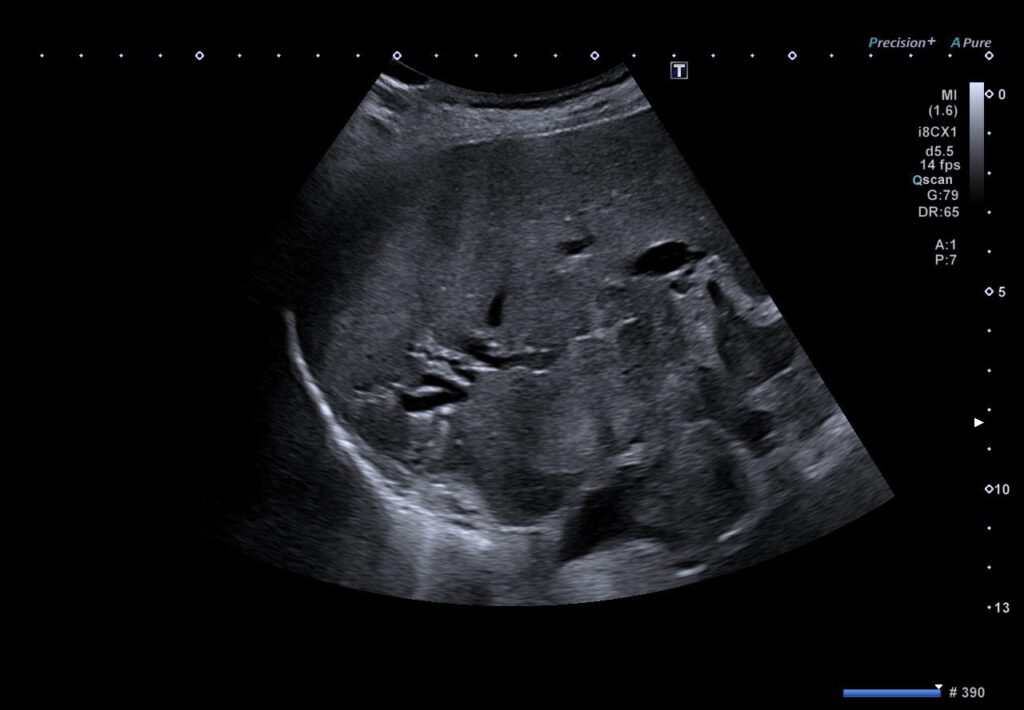

Klinisch erschien ein ikterisches Hautbild, zudem berichtete die Patientin von Gewichtsverlust. Sonographisch wurde ein Tumor in der Gallenblasenloge mit Infiltration des rechten Leberlappens gesehen. In der darauffolgenden ERCP stellte sich der proximale Ductus hepatocholedochus mit großem Füllungsdefekt dar, das Kontrastmittel passierte nur filiform die Engstelle. Letztlich musste die Untersuchung bei frustraner Tumorpassage abgebrochen werden, weswegen sich für die Durchführung einer EUS-geführten Cholangiodrainage entschieden wurde. Transgastrisch wurden die linksseitigen Gallenwege punktiert, intern antegrad gelang die Passage über die Tumorstenose mit nachfolgender Implantation eines partiell gecoverten SEM. Der transgastrische Zugangsweg wurde mittels Hanaro-Stent als Hepatikogastrostomie gesichert. In der sonographischen Abschlusskontrolle war eine Aerobilie wahrzunehmen, die Stents lagen regelrecht.